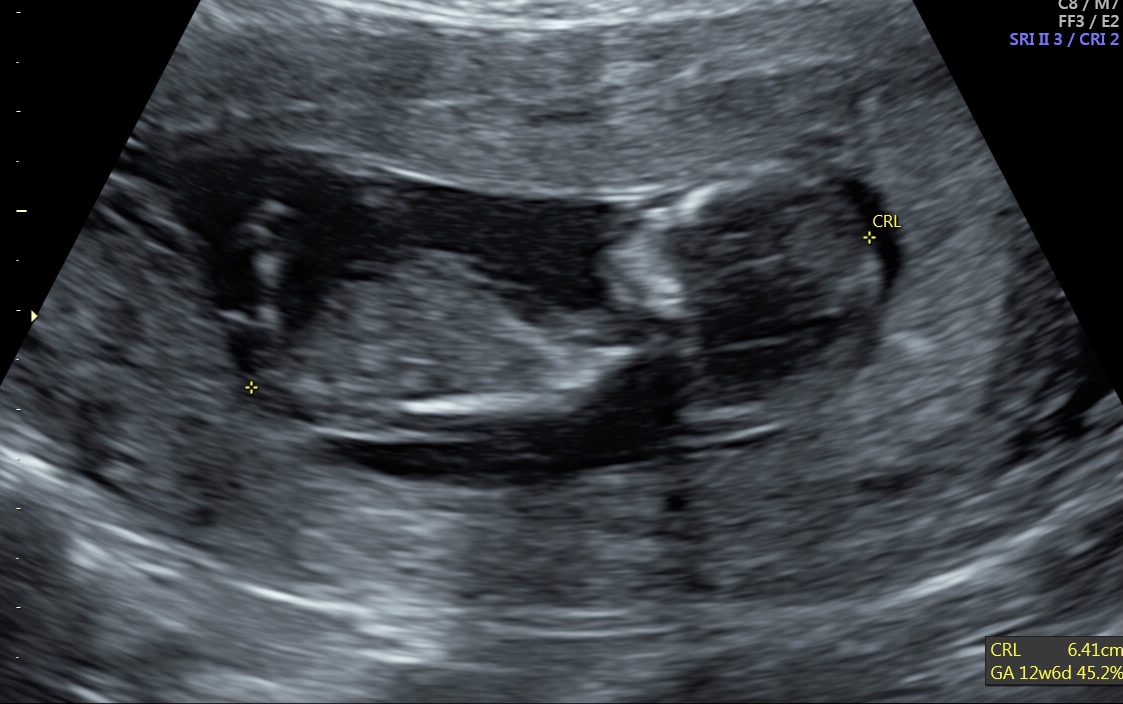

12w5d Any gender clues here? Attachment 39084Attachment 39085

Boy guess

Slight boy lean but not confident.